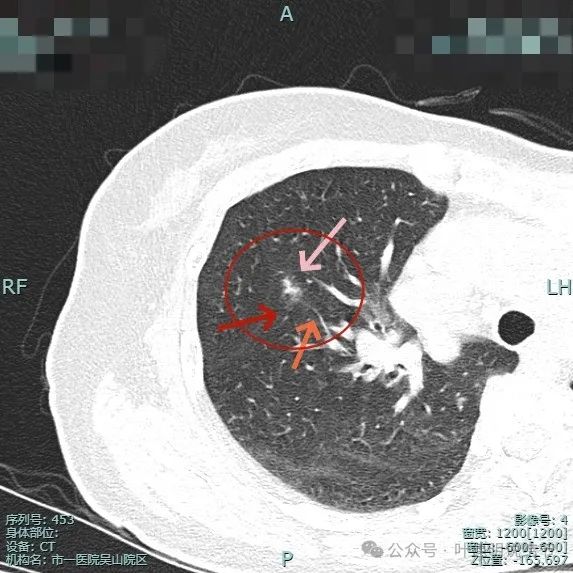

这是患者在市一医院吴山院区检查后的2023年12月时的影像,右上叶磨玻璃密度结节,轮廓较清,密度似乎不是非常淡,表面显毛糙。

这是2024年3月时的平扫影像,密度不纯,表面不平,整体轮廓较清。